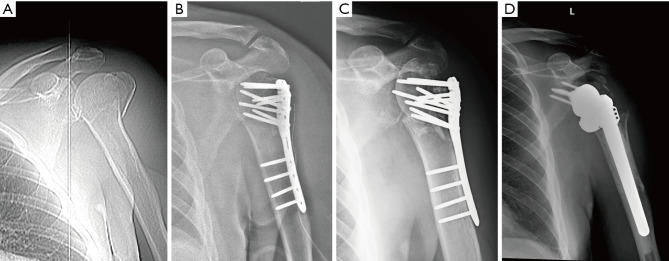

Key content and findings: Patients with minimally displaced fractures should be treated nonoperatively. Internal fixation with intramedullary nailing is a viable option in cases of two-part surgical neck fractures, those with diaphyseal involvement and no significant displacement of the tuberosities, or pathologic fractures. Those elderly patients with displaced three- or four-part PHFs fractures with intact rotator cuff muscles should be treated with locking plate fixation if anatomical reduction of fracture fragments including tuberosity is possible, as the results after union despite avascular necrosis are favorable. Moreover, patients with failed fixation treated with salvage reverse shoulder arthroplasty (RSA) have similar outcomes to RSA for acute PHFs. Hemiarthroplasty should be reserved for select group of young active patients with unconstructable fracture, intact rotator cuff, and good tuberosity bone stock. RSA should be offered as first option for elderly patients with poor bone stock, rotator cuff insufficiency, fracture dislocations, head-split fractures, and severely displaced 3- and 4-part PHFs.

Abstract Image